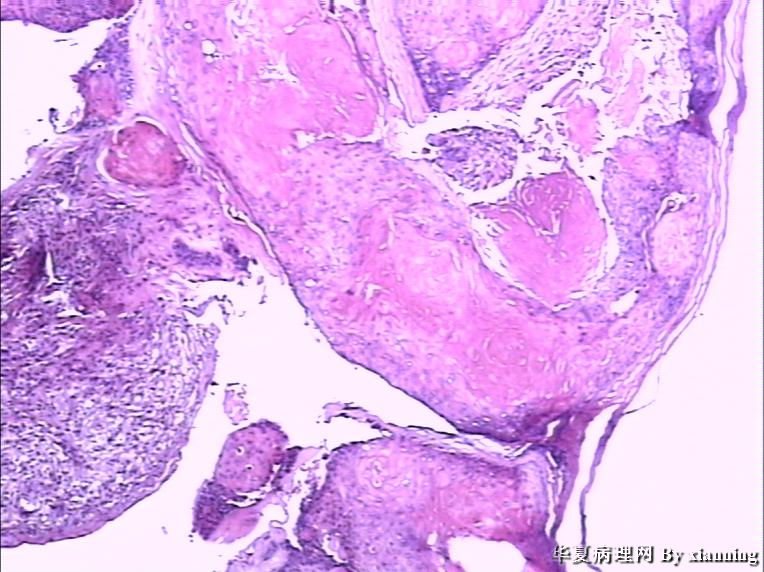

女 50岁 头皮下肿块

巨检:灰白色不规则结节0.9*0.7*0.4cm3,切面灰白色实性质地中等

名称:图2

描述:36580004